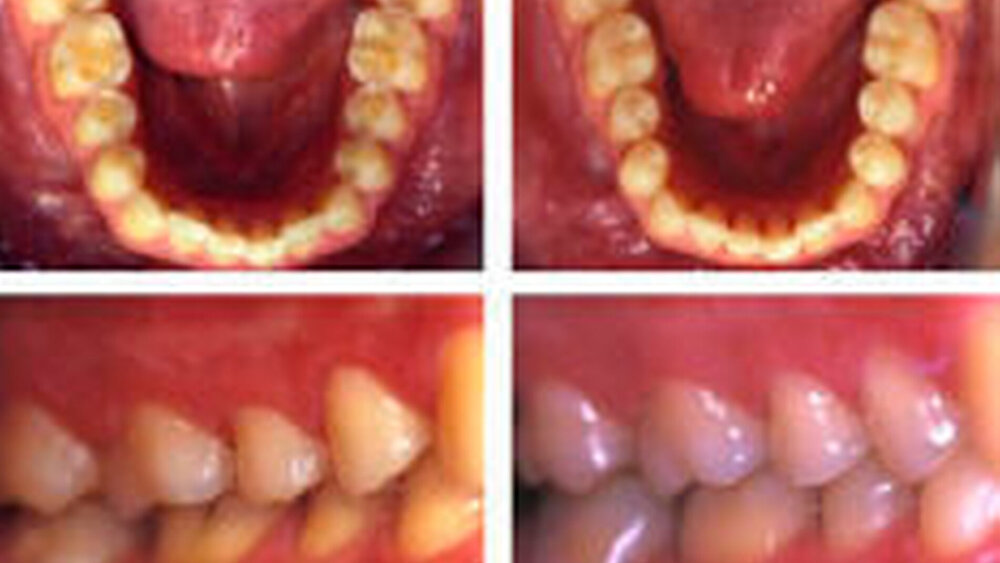

Der Patient war zum Zeitpunkt der Befundaufnahme 34 Jahre alt, allgemeinmedizinisch gesund und Nichtraucher. Dental wurden generalisierte okklusale Erosionen im Ober- und Unterkiefer diagnostiziert, welche stark überempfindlich waren. Anamnestisch konnten als Ursachen ein Reflux während der Pubertät und Bruxismus während der letzten Jahre ermittelt werden (Abbildungen 2a bis e). Die oberen Frontzähne waren mit 19 Jahren überkront worden, da der große palatinale Substanzverlust dem Patienten bereits damals Schmerzen bereitet hatte. Die Stellung dieser Kronen war leider protrudiert und die Länge ungenügend. Aus Kostengründen wurde jedoch auf eine Neuanfertigung verzichtet. Die Seitenzahnbereiche des Oberkiefers wurden in einer ersten Sitzung in der beschriebenen Art und Weise aufgebaut. Der zweite Schritt bestand darin, die Seitenzahnbereiche des Unterkiefers gleichermaßen aufzubauen und eine definitive Okklusion zu etablieren. Der wurzelbehandelte Zahn 46 wurde mit einer Endo-Cerec- Krone versorgt [Bindl & Mörmann, 1999]. Anschließend wurden die Unterkieferfrontzähne direkt mit Komposit verlängert (Abbildungen 3a bis e). Der offene Biss konnte geschlossen und eine Neuanfertigung der oberen Frontkronen vermieden werden. Abschließend wurde eine Michigan- Schiene hergestellt und der Patient über deren Gebrauch instruiert.

Zum Zeitpunkt der Befundaufnahme war der Patient 27 Jahre alt. Sein Allgemeinzustand war gut. Diagnostisch wurden generalisierte okklusale Erosionen, vor allem im Unterkiefer, festgestellt. (Abbildung 4). Anamnestisch konnte mit einer fünftägigen Diätanamnese ein hoher Red-Bull-Konsum ermittelt werden, welcher aber nicht direkt als Ursache angeprangert werden darf, da an den Oberkiefer-Frontzähnen bukkal keine Erosionen vorlagen. Es wurden keine weiteren pathologischen Befunde erhoben, sodass von einem früher eingetretenen idiopathischen Zahnhartsubstanzverlust ausgegangen werden musste. Der Patient hatte einen Tiefbiss. An den Frontzähnen wurden deshalb Schlifffacetten und palatinale Einbissrillen festgestellt. Zunächst wurden die Seitenzahnsegmente des Unterkiefers mithilfe einer Miniplastschiene in der oben beschriebenen Art und Weise in zwei Sitzungen aufgebaut. Die distalen Molaren des 3. und 4. Quadranten wurden ohne Hilfsmittel direkt modelliert. Bei den Oberkieferseitenzähnen wurden nur die Erosionen aufgefüllt, ohne den Biss weiter zu heben. Als letzter Schritt erfolgte in einer weiteren Sitzung der direkte Aufbau der Oberkieferfrontzähne (Abbildung 4).